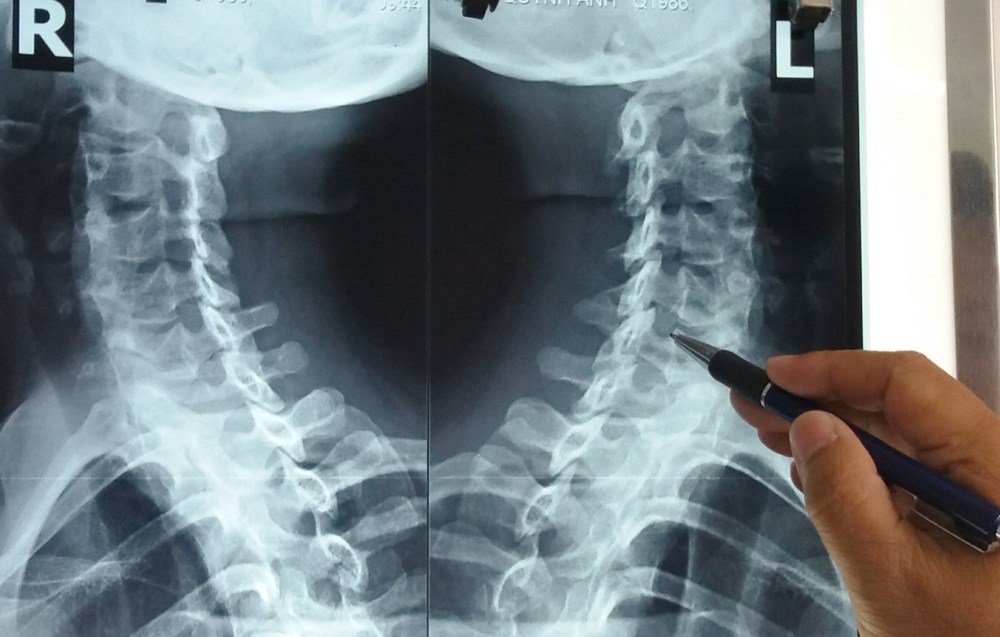

Hình ảnh X-quang nhận diện thoái hóa cột sống cổ.